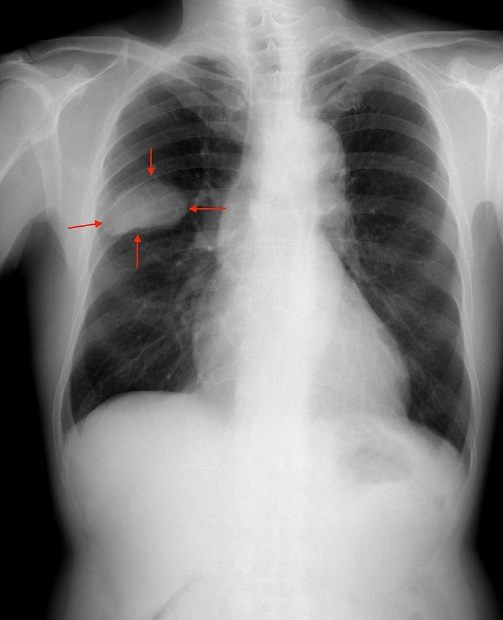

Tumoră - cancer pulmonar

Unul dintre cele mai agresive cancere este cel pulmonar microcelular, din pricina detecţiei tardive şi a capacităţii de metastazare până este descoperit. El devine sesizabil atunci când pacientul prezintă simptome (tuse cu sau fără sânge, febră, scădere în greutate, oboseală etc.) sau când are o dimensiune suficient de mare astfel încât să fie observat pe radiografie.